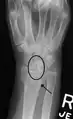

X-ray images indicate scapholunate ligament instability when the scapholunate distance is more than 3 mm, which is called scapholunate dissociation.[7] A static scapholunate instability is generally readily visible, but a dynamic scapholunate instability can only be seen radiographically in certain wrist positions or under certain loading conditions, such as when clenching the wrist, or loading the wrist in ulnar deviation.[6]

In order to diagnose a SLAC wrist you need a posterior anterior (PA) view X-ray, a lateral view X-ray and a fist view X-ray.[8] The fist X-ray is often made if there is no convincing Terry Thomas sign. A fist X-ray of a scapholunate ligament rupture will show a descending capitate bone. Making a fist will give pressure at the capitate, which will descend if there is a rupture in the scapholunate ligament.

- Scapholunate ligament disruption associated with a Colles' fracture